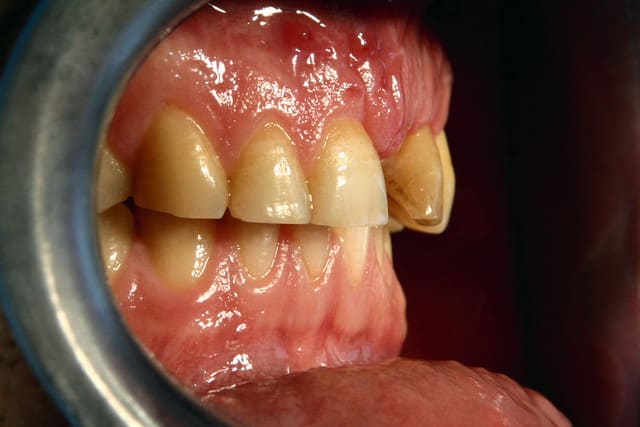

Img 5830 sx42wd - Eugenol

Img 1173 tih5r1 - Eugenol

tres belle photos.....avec ou sans flash annulaire??

merci!

la premiere etant une prise de teinte, je l' ai faite en lumière naturele, la seconde a ete faite sous scialytique. je dois recevoir mon flash annulaire dans 10 jours (le sigma...360 euro "seulement") pour ce qui est du reste, c' est un 10D avec un tamron 28/75....donc, pour ceux qui prendront un 20D avec une focale fixe et le flash annulaire d' emblée, le résultat sera plus piqué. (en fait, je n' avais pas assez d' argent pour acheter tout d' emblee il y a 15 mois...) ...mais j' apprecie mon choix un peu plus chanque jour!